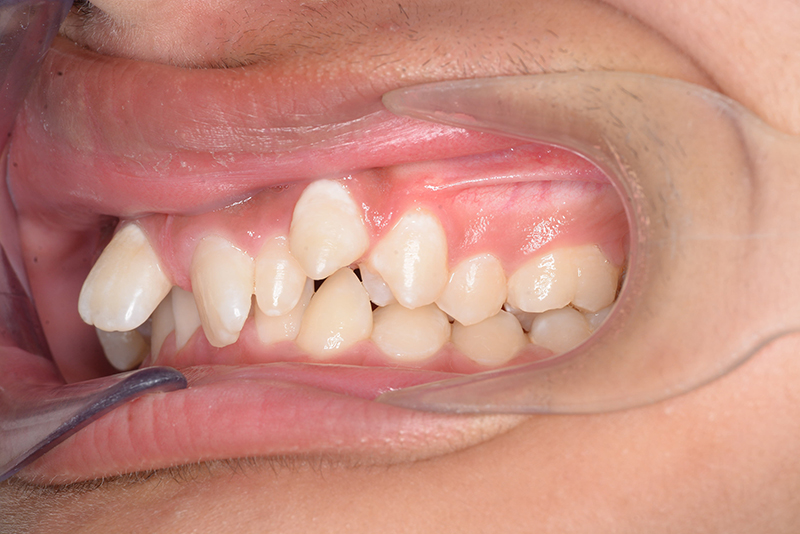

動的治療終了時

FP・IOP

批評・予后 側貌はconcave typeであり、下顎歯列は叢生が少ないこと、右上3欠損、左右上2は矮小歯であることを考慮して右上C、左側2抜歯とした。治療後はアンテリアレシオの調和を図るべく右上2は暫間的修復(CR)にて歯冠幅径を大きくしている。保定終了後には同部位は最終補綴を装着する予定である。